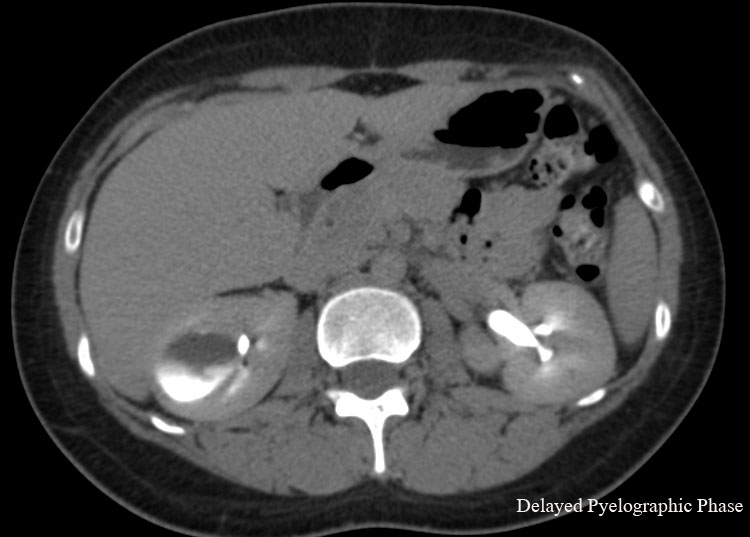

Caliceal Diverticulum